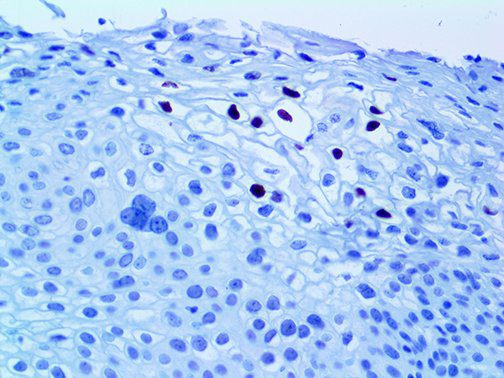

It is the ICU physician who is most likely to witness one of the deadliest manifestations of the abnormal immunological response, the cytokine storm syndrome (CSS). This response is also referred to by some as the cytokine release syndrome (CRS). CSS is characterized by continuous activation and expansion of macrophage and lymphocyte populations, which secrete large amounts of cytokines, causing the cytokine storm. This massive cytokine release is akin to hemophagocytic lymphohistiocytosis (HLH) disease, a syndrome characterized by initial unchecked and persistent activation of cytotoxic T lymphocytes and NK cells.

Clinical and laboratory manifestations of HLH include fever, enlarged liver and/or spleen, neurologic dysfunction, coagulopathy, liver dysfunction, cytopenias (i.e., low levels of erythrocytes, leukocytes, and/or platelets), hypertriglyceridemia, hyperferritinemia, hemophagocytosis, and eventually diminished NK cell activity as the immune system becomes progressively paralyzed. HLH can be familial (primary HLH) or secondary to another disease process (sHLH), such as rheumatic disease, in which it is referred to as macrophage activation syndrome (MAS, characterized by elevated ferritin).